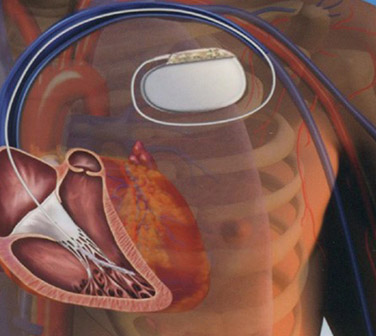

¿Tiene interés hablar hoy en día del desfibrilador automático implantable subcutáneo? Todos conocemos la importancia que tiene el desfibrilador convencional, que es un generador que se implanta encima del pectoral y se conecta con unos electrodos que van directamente...